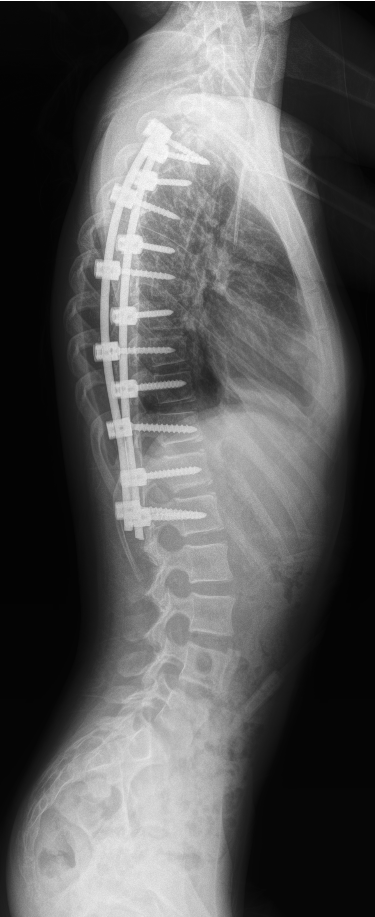

全自动全景成像(选配)

三次点击,两个步骤,一气呵成

全过程一分钟内完成,摄影条件智能设定,根据不同体厚智能曝光补偿,宽幅窄缝按需选择,无需往返机房调整机架位置,一气呵成自动全景成像